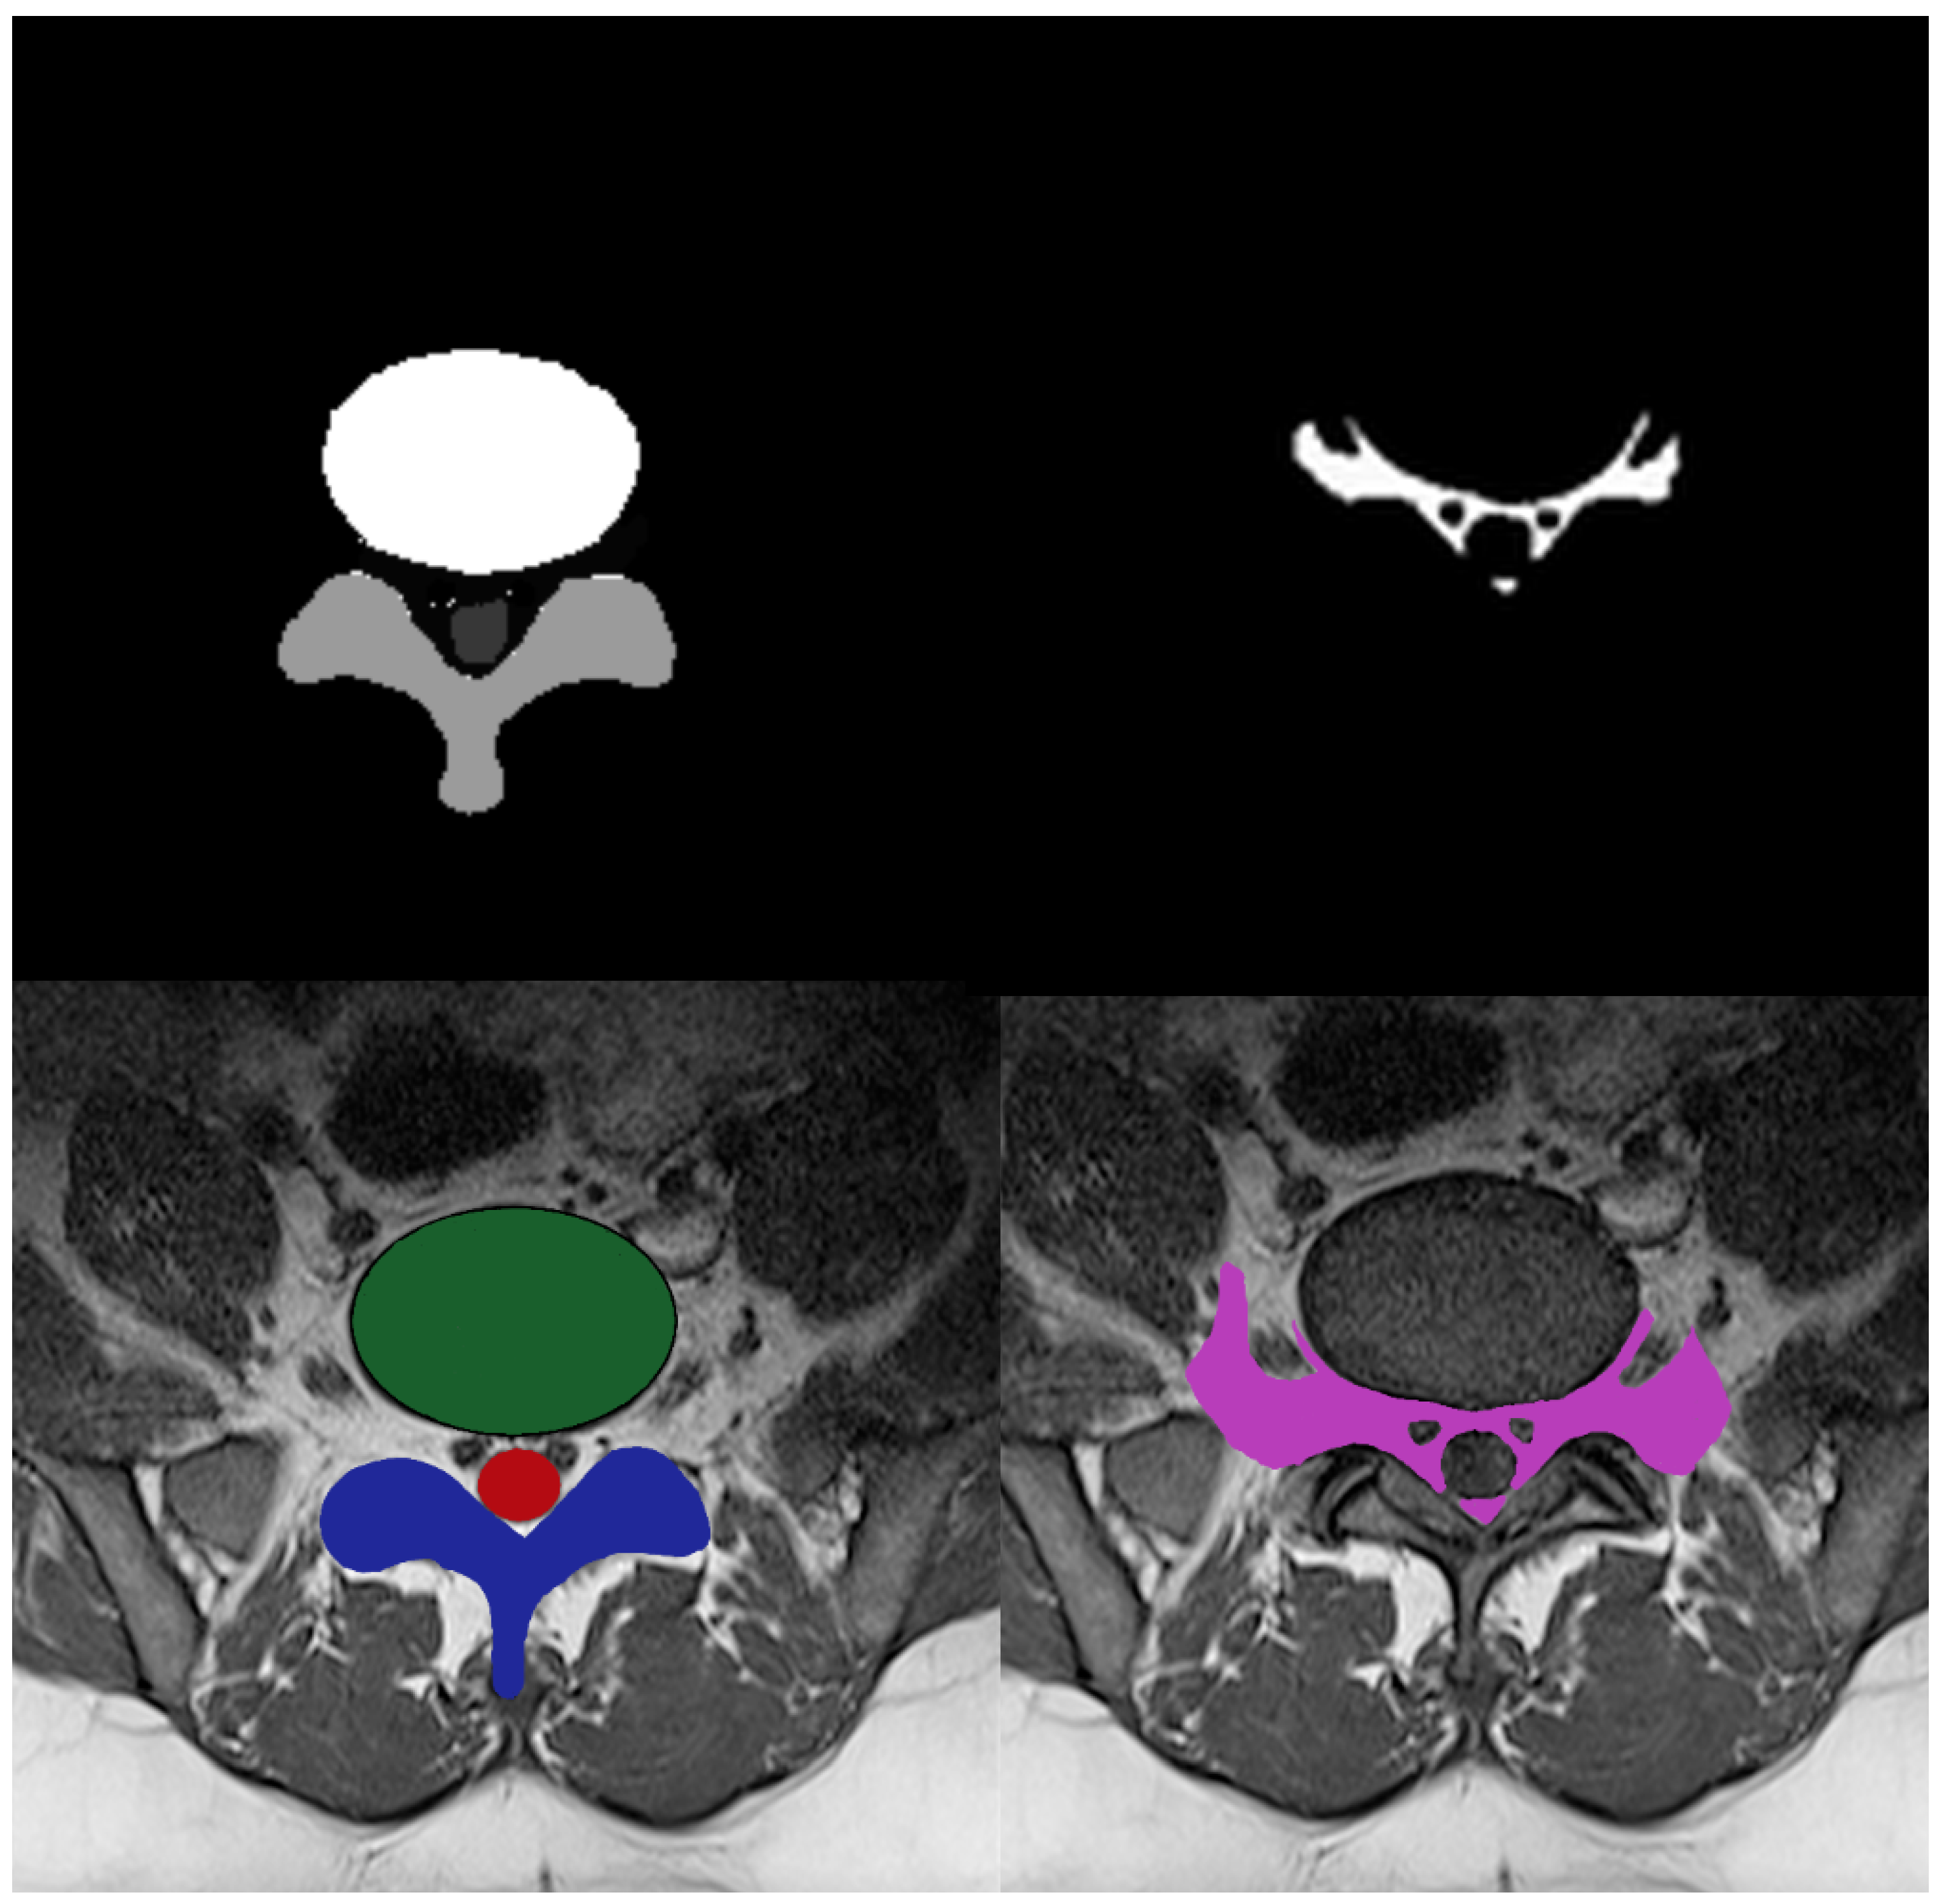

Diagnostics Free FullText Nerve Root Compression Analysis to Find Lumbar Spine Stenosis on How To Detect Lumbar Spine Obtaining a clinical diagnosis of the underlying cause of lower back pain, not merely a description of the symptoms, is important in guiding treatment. Sometimes, the ligament at the back of the lower spine, also called the lumbar spine, gets too thick. Mri of the spine can show spinal alignment, lumbar disk herniation,. A contrast agent that helps highlight certain. How To Detect Lumbar Spine.